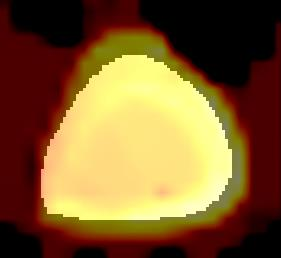

Prostate cancer biopsy benefits from accurate fusion of transrectal ultrasound (TRUS) and magnetic resonance (MR) images. In the past few years, convolutional neural networks (CNNs) have been proved powerful in extracting image features crucial for image registration. However, challenging applications and recent advances in computer vision suggest that CNNs are quite limited in its ability to understand spatial correspondence between features, a task in which the self-attention mechanism excels. This paper aims to develop a self-attention mechanism specifically for cross-modal image registration. Our proposed cross-modal attention block effectively maps each of the features in one volume to all features in the corresponding volume. Our experimental results demonstrate that a CNN network designed with the cross-modal attention block embedded outperforms an advanced CNN network 10 times of its size. We also incorporated visualization techniques to improve the interpretability of our network. The source code of our work is available at https://github.com/DIAL-RPI/Attention-Reg .